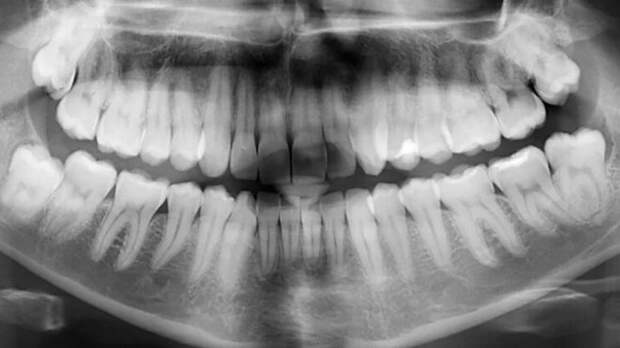

Еще в 2018-м исследователи из Вашингтонского университета(США) объявили о начале работ над принципиально новым средством для восстановления эмали зубов. В его основе лежит изучение возможностей применения пептидов для «перезапуска» активности амелобластов. И вот они наконец достигли успеха – новое средство успешно «отремонтировало» зуб без дополнительного вмешательства.